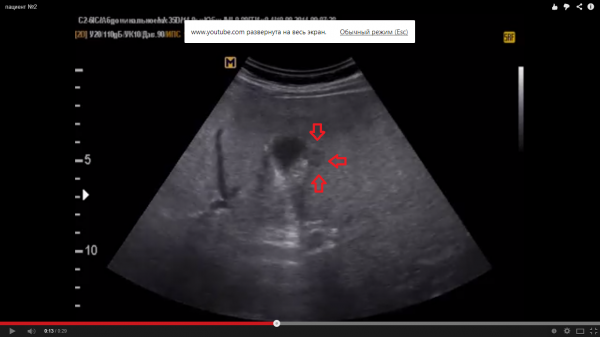

Пациентов - два. № 1 - женщина 60 лет № 2- мужчина 50 лет

Согласен. Очень часто встречается,особенно, в IV сегменте.Это могут быть не измененные участки на фоне диффузных изменений паренхимы печени (таких как жировой гепатоз).

Тоже соглашусь с версией, что это очаги сохраненной ткани печени на фоне жирового гепатоза. Часто такое встречается возле желчного пузыря и вдоль крупных сосудистых ветвей!

Я тоже за жировой гепатоз с нормальным участком паренхимы печени. Но определение гипостеатоза встречаю в первые, разве так называют нормальную печёночную ткань в данной ситуации?